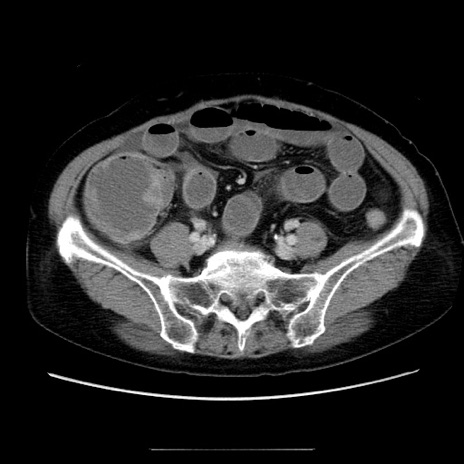

冠状断像

【症例】70歳代女性

【主訴】お腹が張る

【現病歴】1週間くらい前から腹部膨満の自覚あり。昨日夜から増悪したため、本日救急外来受診。

【身体所見】意識清明、BT 36.5℃、BP 165/106mmHg、HR 80bpm、SpO2 98%、腹部:膨満、軟、自発痛・圧痛なし、触診にて不快感あり、腸蠕動音:減弱

【データ】WBC 12600、CRP 1.04